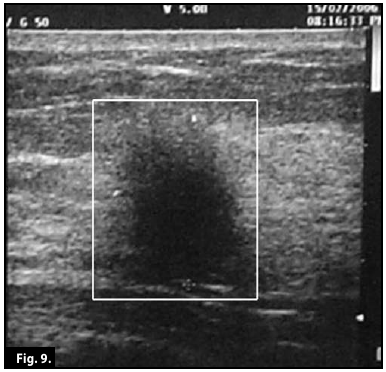

Ultrasound scan...